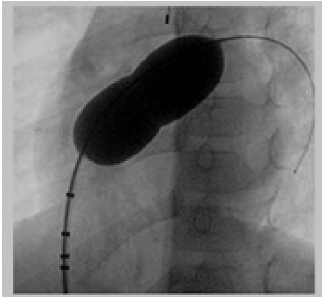

- Đẩy bóng trên guidewire cứng lên lỗ thông liên nhĩ. Bơm bóng bằng thuốc cản quang tại vị trí lỗ TLN. Ngừng bơm khi xuất hiện rõ eo bóng.

- Đo kích thước eo bóng trên phim chụp mạch dựa vào các điểm mốc trên bóng.

- Xác định kích thước lỗ TLN theo ba phương pháp: trên phim chụp mạch, trên siêu âm qua thực quản, và phương pháp đo trực tiếp ở ngoài.

Hình 1. Đo kích thước lỗ thông bằng bóng